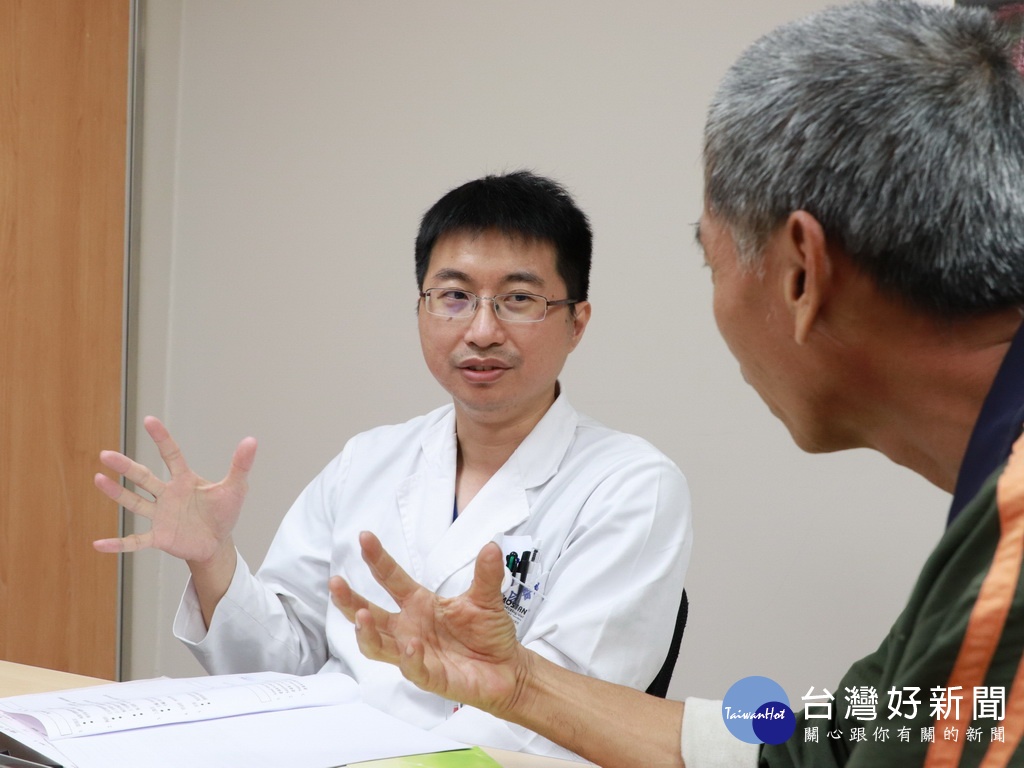

使用葉克膜救回的男子。林重鎣攝

大里仁愛醫院心臟內科李明峯醫師表示,心臟病總是來得又急又快,症狀是會喘,醫師只有幾小時、幾分鐘,甚至幾秒鐘的救命時間,當心臟衰竭發生血壓低、意識不清時,如果來不及到醫院裝葉克膜幾乎是無法挽救生命。黃姓男子發作時血壓降低、意識模糊,原因是心臟衰竭的程度無法打出充足的血液量,很有可能他自己沒有意識到會這麼嚴重,因此一發作就幾乎快沒命了。他最幸運的一點就是「及早就醫」,趁著腦部尚未受損前接受治療,最後是一個非常圓滿的結局。

針對心臟衰竭患者,李明峯醫師提醒,切記要定時回診,按時服藥,不能吃太鹹的東西,注意觀察小腿有無水腫現象,平常一天喝不超過1000CC的水,每天也要量體重、血壓和心跳,做成記錄拿給醫師看,作為診斷病情的參考。

李明峯醫師指出,心臟病的高危險族群包括:高血壓、糖尿病、心臟瓣膜有問題,或75歲以上的長者,如果罹患心臟病,記得要定期回診和服藥,確保健康。另外,很多心臟衰竭與心肌梗塞病例好發於50~60歲民眾身上,呼籲大家平常要量血壓,還有人因為泡溫泉而發生這兩種症狀,所以建議民眾泡溫泉不要泡太久,避免發生憾事。